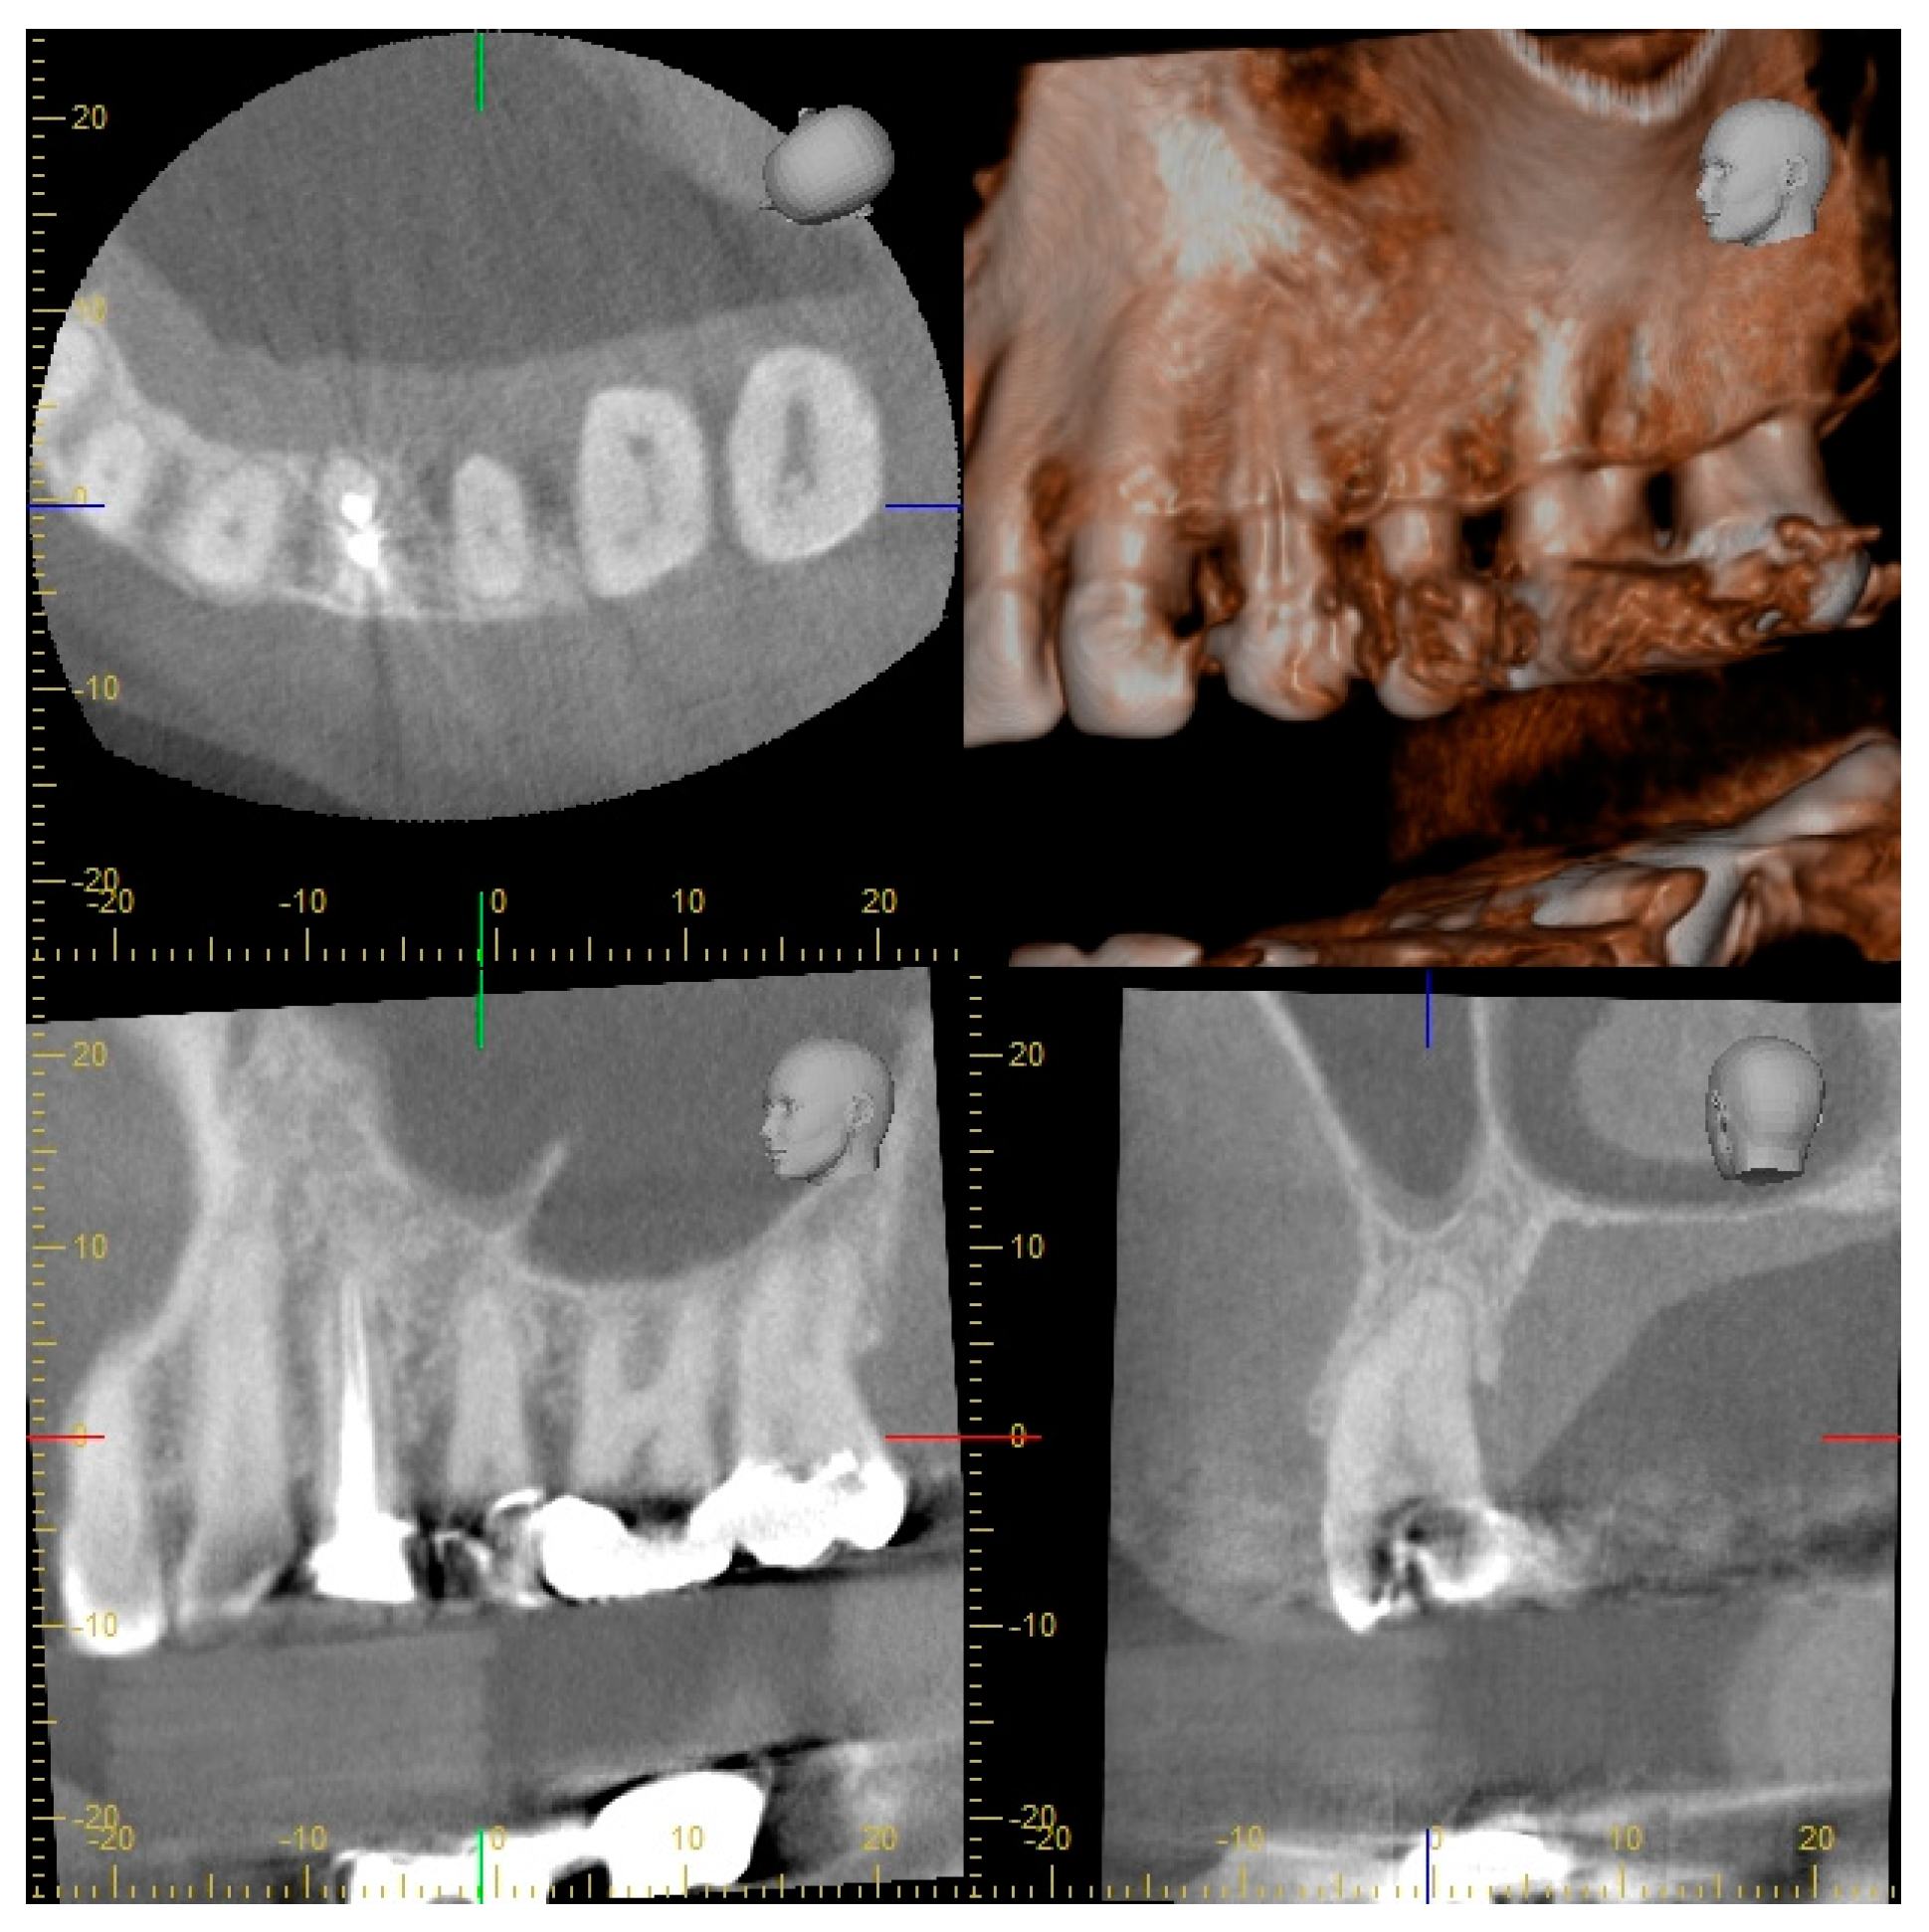

2.2. Radiographic Methods

2.3. Analysis of Radiographic Images